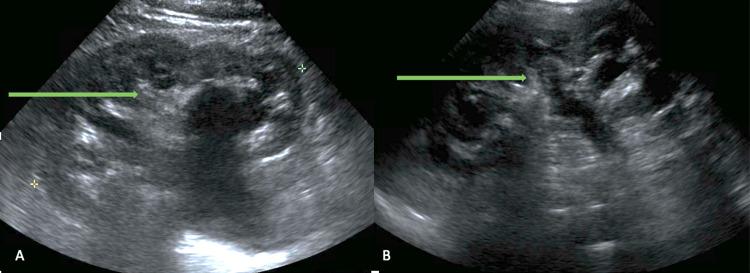

Kidneys influence the production of red blood cells by secreting most of the erythropoietin (EPO) in adults. Consequently, renal diseases often impact erythropoiesis and hemoglobin levels. Chronic kidney diseases lead to anemia due to EPO deficiency. However, erythrocytosis can occur in patients with cystic diseases of the kidney and renal artery stenosis due to upregulation of hypoxia-inducible factors (HIFs) and increased EPO production. Here, we present a patient with secondary polycythemia who was found to have atonic bladder and hydronephrosis. Resolution of hydronephrosis led to the reversal of erythrocytosis, highlighting the intricate regulation of red cell production.

在成年人中,肾脏通过分泌大部分促红细胞生成素(EPO)来影响红细胞的生成。因此,肾脏疾病常常会影响红细胞生成和血红蛋白水平。慢性肾脏疾病会因EPO缺乏导致贫血。然而,由于缺氧诱导因子(HIFs)上调和EPO生成增加,患有肾囊性疾病和肾动脉狭窄的患者可能会出现红细胞增多症。在此,我们报告一名患有继发性红细胞增多症的患者,该患者被发现存在无张力膀胱和肾积水。肾积水的缓解导致红细胞增多症的逆转,突出了红细胞生成的复杂调节机制。